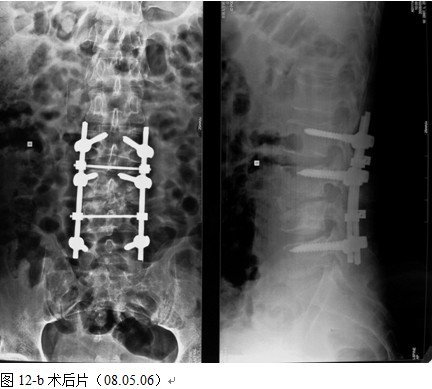

以病变椎体为中心,作一后正中切口,显露病椎棘突、椎板、关节突以及上下需要固定的正常椎体,根据后凸畸形的严重程度在C 型臂协助下确定进钉角度和方向,置入椎弓根钉,椎弓根钉固定的方法:病灶上下相邻正常椎体置入,当病椎骨质破坏不超过1/3或未累计椎弓根时置入相对较短的钉子,一般长度为35mm,当骶1椎体有破坏时,根据骨质的情况确定入钉的方向,将病椎上、下关节突关节切除,自椎间孔显露病灶,直视神经根状态下进行病灶清除和椎管减压,可将干酪样物,死骨,坏死的椎间盘大部分清除,解除硬膜囊的压迫,必要者可双侧同时病灶清除,减压。无钛棒状态下用椎体撑开器轻柔牵开,采用前路撑开结合后路固定维持有限撑开或加压缓慢矫正脊柱后凸畸形,特别注意是由于结核患者骨质疏松,不可用钉棒大力撑开,否则钉子拔出可能性较大。要前路撑开加后路加压来达到矫形的目的。撑开后,缺损空间增大,大部分用手指可触及缺损内的情况,能进一步彻底清除病灶及对侧的病灶,反复用异烟肼盐水混合液冲洗病灶,凿出植骨床,植骨时需注意植骨块要采用“平进竖植”方法,循序用植骨打入器和辅助器械缓慢植入否则易导致神经根损害。植骨完成后再次采用内固定适当加压促使骨块稳定及融合,如果病灶中的脓液稀薄较多时,在病灶中留置一根硬膜外管,术后注射异烟肼,每周两次,以提高局部的药物浓度,在对侧椎板,关节突间植骨,病灶内留置链霉素2.0g ,放置引流管,闭合伤口。

本组手术用时间3~4h , 平均3.5h 。术中出血300~500ml , 平均约350ml 。术后症状完全缓解,无神经功能障碍加重等并发症,1例营养差的老年患者伤口出现窦道,1例因肝功能差,术后未口服抗痨药,伤口出现窦道,经换药后二期愈合,其余病例伤口均一期愈合。马尾神经受损的患者术后基本恢复正常。术后一周后凸角平均 5.4°后凸畸形平均矫正90%以上, 最终后凸角平均8.3°,后凸角度平均丢失4.2°。随访3个月有87%(40/46)有骨痂形成,6个月91.3%(42/46)明显骨性愈合(见图),其余4例9-12个月内愈合,随访时间3-32个月,平均11个月,46例患者中2例在术后2个月和3个月时背部形成脓肿,换药后治愈。2例出院1月后并发结核性脑膜炎,治疗后好转。1例因椎弓根钉偏外,刺激神经根,5个月后从侧方脱出,疼痛加重,因前后路植骨完全愈合,取出后症状完全缓解。